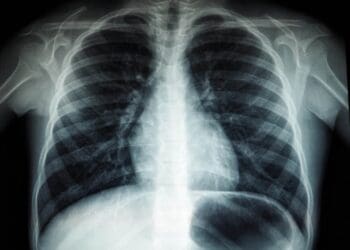

Pneumonia is an infection that causes inflammation in the air sacs of one or two lungs. The air sacs…

It’s one of the most extensively used tests in the medical community. And despite being a common…